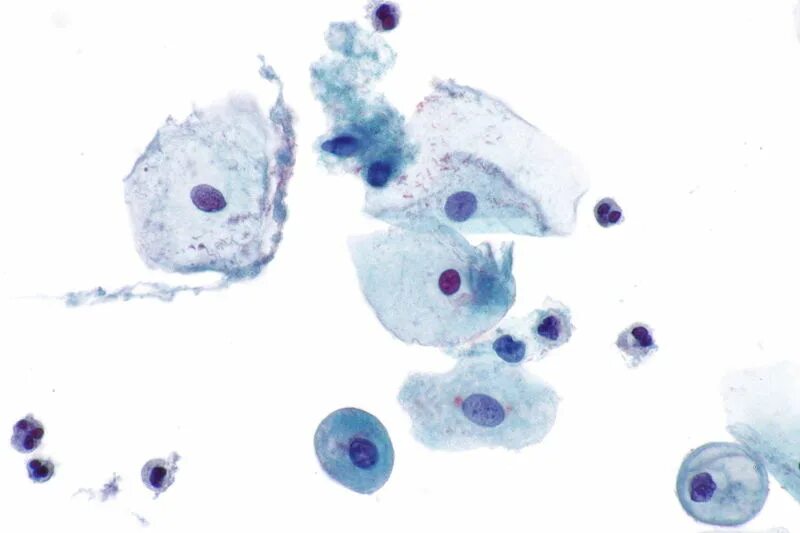

3 тип мазка